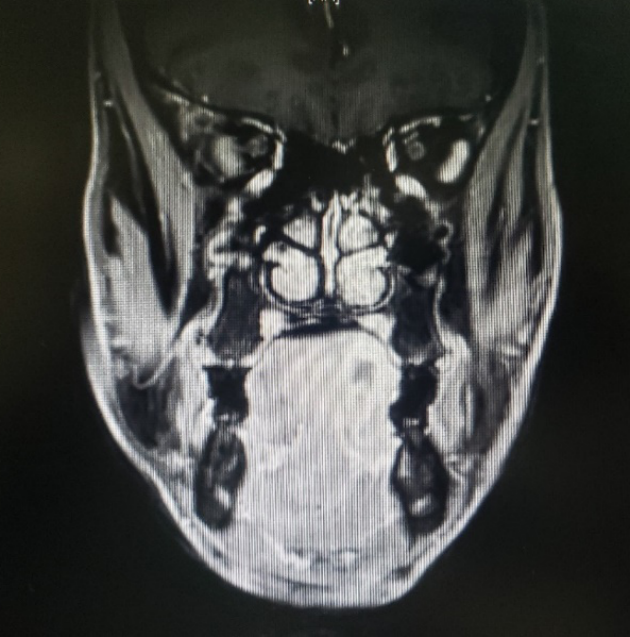

图一:患者的MRI

图二:患者的MRI

图三:患者的MRI